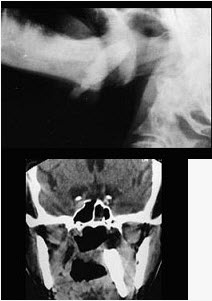

67岁男性患者,咽喉部异物感3年余,从小经常出现咽喉部疼痛伴发热,行X线及CT检查如图所示,请选择正确的描述和结论()。

A、侧位示与下颌骨部分重叠的条形致密影

B、CT示右侧下颌骨内侧咽旁间隙见条形致密影

C、右侧扁桃体结石

A,B,C